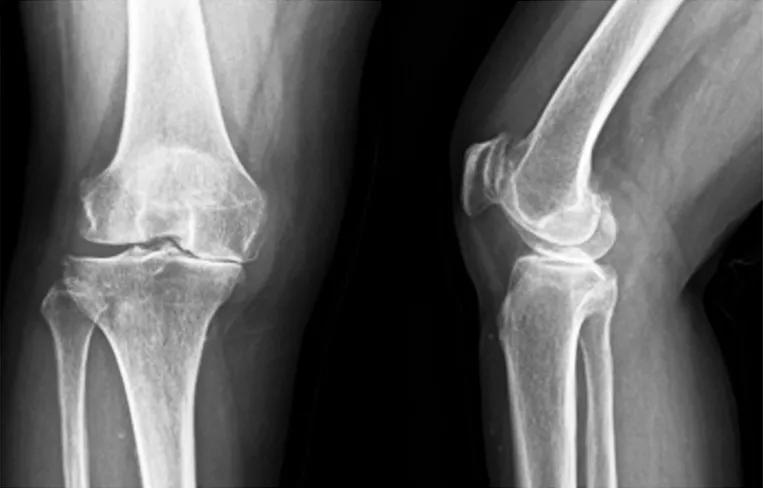

(2)65岁女性患者,以右膝关节疼痛3年、加重半年为主诉入院,入院查体右下肢内翻畸形8°,膝关节内侧间隙压痛阳性,外侧无压痛,浮髌试验阴性,髌骨研磨试验阴性,抽屉试验阴性,ROM10°~130°,诊断为右膝关节前内侧骨关节炎,行Oxford活动平台内侧单髁置换术。术后24h内间断冰敷,给予预防感染、消肿止痛及抗凝治疗,术后24h康复师指导助行器辅助下床活动,术后1个月膝关节HSS评分由62分升至81分,KSS评分由50分升至85分,内侧疼痛消失,手术效果良好。手术前后影像学资料见图3~4。

图3术前 X线片示内侧间隙呈骨对骨改变

图4术后 X线片示假体位置良好,大小合适,活动垫片在位